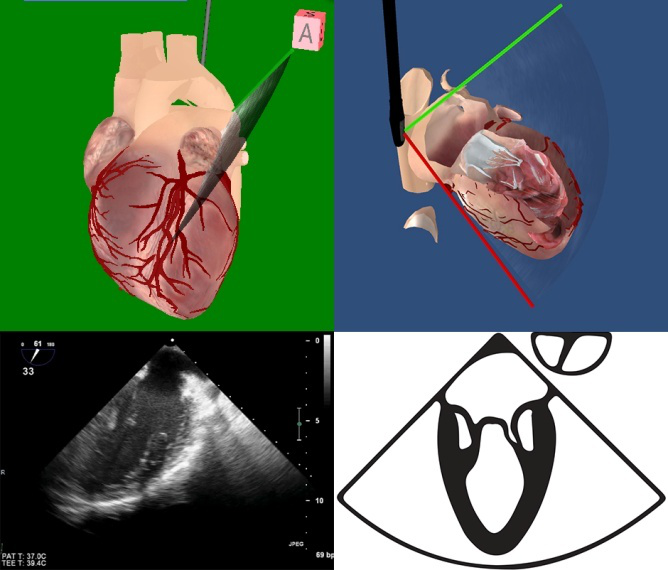

右室流入-流出道 (ME RV inflow-outflow) TEE-Focus基本切面

60°~90° |

|

在主动脉瓣短轴切面的基础上,推进探头显示右心房、三尖瓣、右心室流入道;右心室流出道、肺动脉瓣、主肺动脉。

该切面不显示主动脉瓣,而现实左室流出道。

可用来测量三尖瓣环的最大径。

2.右室流入流出道切面(图5-2) ①右心房大小、房壁厚度是否正常,舒缩运动是否正常;②三尖瓣开闭运动是否正常,有无穿孔及赘生物;③右心室流入道是否通畅;④右心室大小,室壁厚度是否正常,舒缩运动是否正常;⑤右心室流出道是否有梗阻;⑥肺动脉瓣开闭是否正常,有无赘生物;⑦肺动脉管壁、管腔是否正常;⑧腔内血流是否正常。